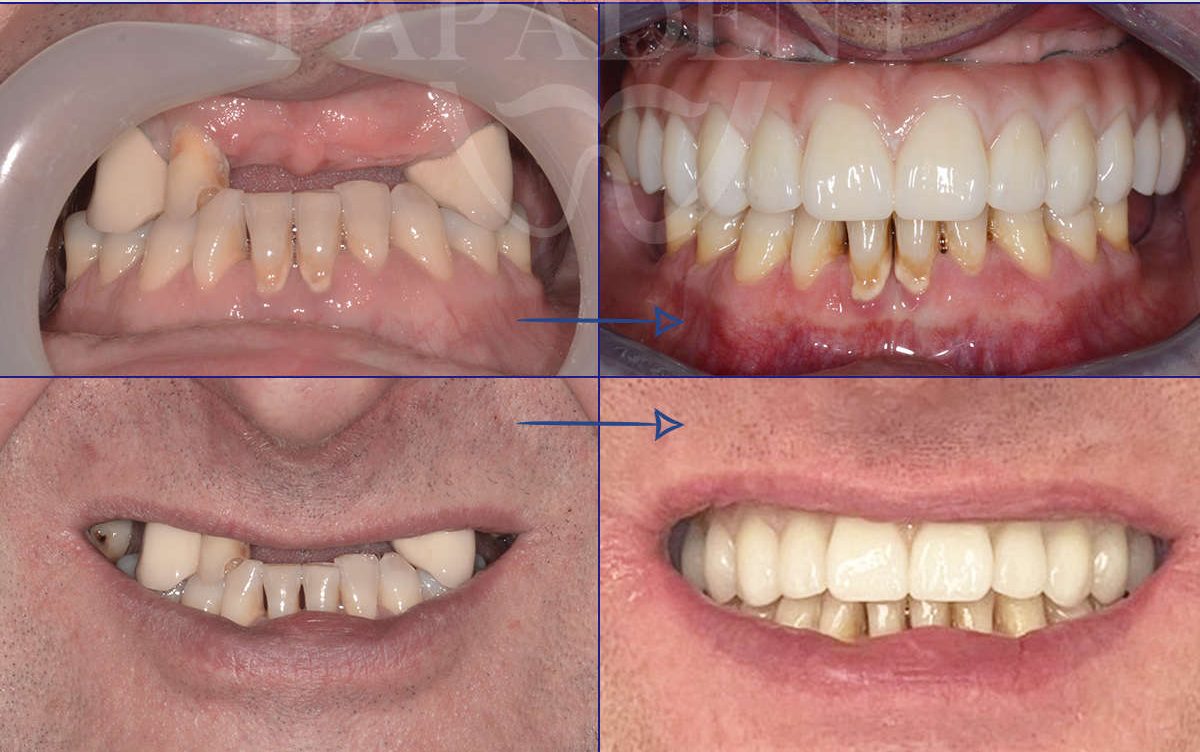

„All-on-4“ yra pažangi dantų implantavimo technika, leidžianti atkurti visą viršutinio arba apatinio žandikaulio dantų lanką vos su 4 implantais. Ant šių implantų fiksuojamas nuolatinis dantų protezas, kuris užtikrina ne tik estetišką šypseną, bet ir pilnavertę kramtymo funkciją. Šis metodas yra greitas, komfortiškas ir daugelio specialistų pripažįstamas kaip vienas efektyviausių sprendimų bedančiams žandikauliams netekus daugelio ar visų dantų.

- Dantų protezai ant 4 implantų vos per 24 – 48 val. Ir turite naujus visus dantis!

- Išsaugosite žandikaulį, taisyklingą sąkandį ir drąsiai šypsositės. Valgysite be apribojimų.